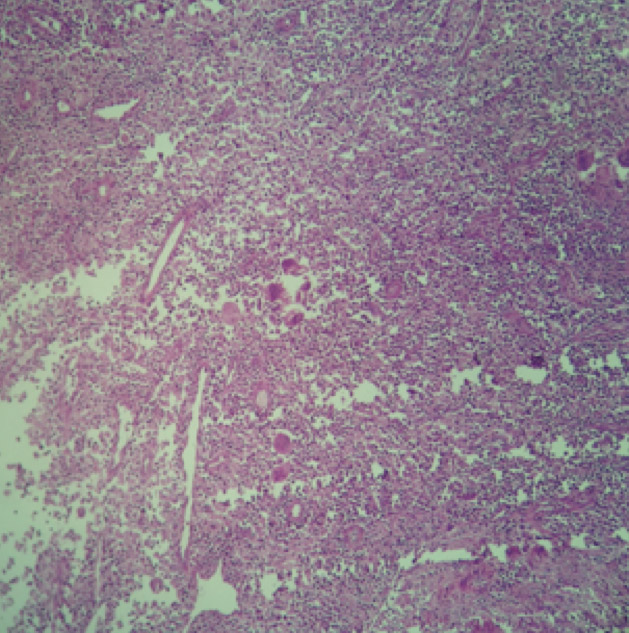

Xanthogranulomatous Cholecystitis

Histiocytes mixed with inflammatory cells MGG stain

Sheets of foam cells